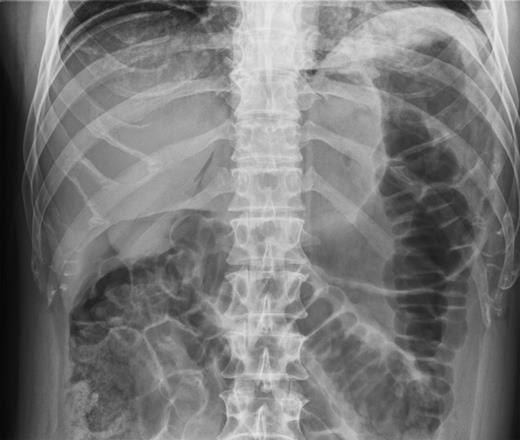

He was taken for urgent laparotomy to evacuate the free gas and aid diagnosis. The bowel was extensively examined and no evidence of perforation was found. The abdominal wall was closed and he returned to the ward. Subsequent X-rays showed that the pneumoperitoneum had resolved. Post-operatively his CRP level was 226 and he went into ileus requiring nasogastric tube placement (Fig. 3). With recurrence of normal bowel activity and with settling of his symptoms, he was discharged.